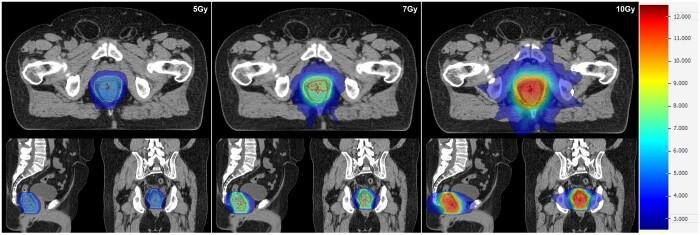

Ten patients previously treated with curative-intent standard long-course radiotherapy (50 Gy/25#) were re-planned. Boost target volumes () were delineated semi-automatically using 40th centile intra-tumoural apparent diffusion coefficient value with expansions (anteroposterior 11 mm, transverse 7 mm, craniocaudal 13 mm). Biased-dosed combined plans consisted of a single-fraction volumetric modulated arc therapy flattening-filter-free (VMAT-FFF) boost (phase 1) of 5, 7, or 10 Gy before long-course VMAT (phase 2). Phase 1 plans were assessed with reference to stereotactic conformality and deliverability measures. Combined plans were evaluated with reference to standard long-course therapy dose constraints.

Phase 1 BTV dose targets at 5/7/10 Gy were met in all instances. Conformality constraints were met with only 1 minor violation at 5 and 7 Gy. All phase 1 and combined phase 1 + 2 plans passed patient-specific quality assurance. Combined phase 1 + 2 plans generally met organ-at-risk dose constraints. Exceptions included high-dose spillage to bladder and large bowel, predominantly in cases where previously administered, clinically acceptable non-boosted plans also could not meet constraints.